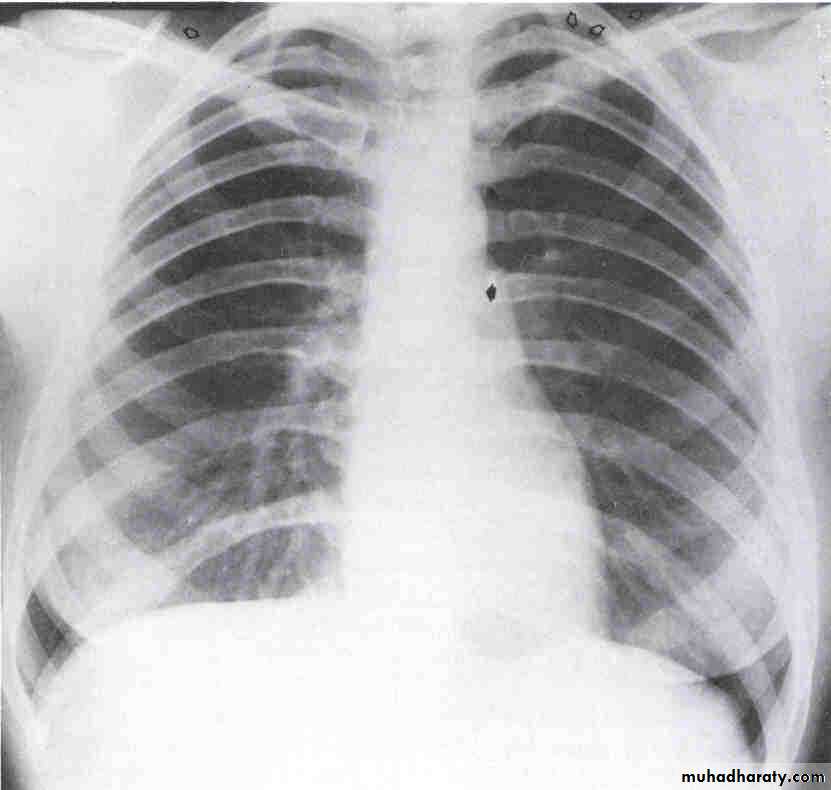

Chest X-ray

Look for Heart sizePulmonary vascular markings

COPD, pneumonia, Pneumothorax, widened mediastinum

Pleural effusions

Chest X- ray